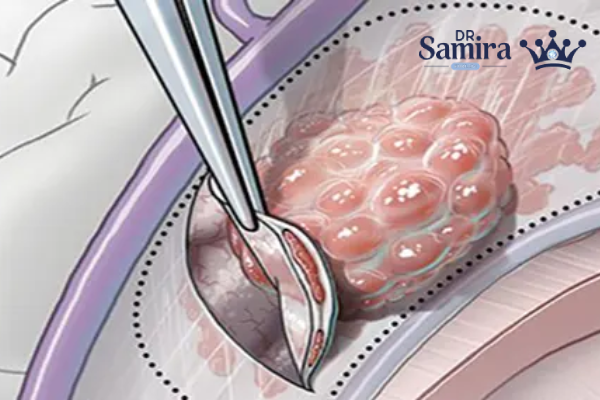

با روش جراحی: خط اول درمان

جراحی اصلی ترین و موثرترین درمان برای مننژیوم آتیپیک است. هدف جراحی، برداشت بیشترین حجم ممکن از تومور بدون آسیب به ساختارهای حیاتی مغز و اعصاب است.

برداشت کامل طبق طبقه بندی «سیمپسون» (Simpson grade I-II) بهترین شانس را برای کنترل بیماری میدهد. با این حال، در بسیاری از موارد به دلیل نزدیکی تومور به عروق یا اعصاب مهم، برداشت کامل امکان پذیر نیست. در این شرایط، برداشت ناقص (Subtotal resection یا STR) انجام میشود و سپس درمانهای تکمیلی مانند رادیوتراپی مورد نیاز خواهد بود.